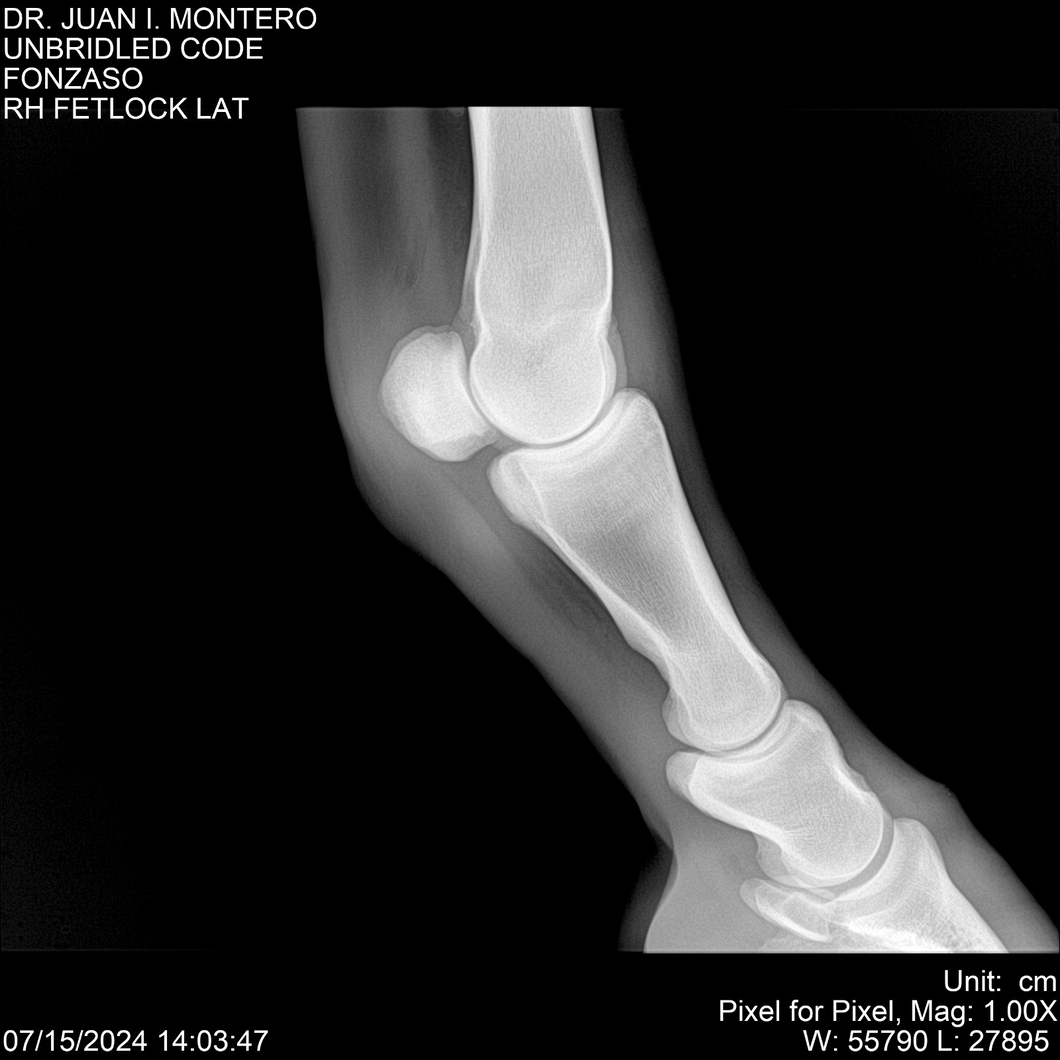

• Empresa: Abelenda N. R., Walter Hugo